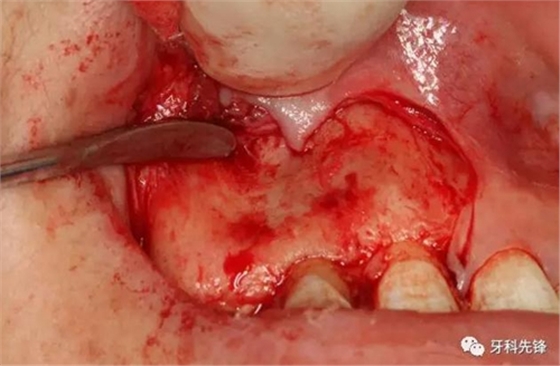

圖11.取出囊腔內(nèi)的致密團塊。

圖12. 取出沒有完全鈣化形成的牙齒。

圖13.摘除囊壁。